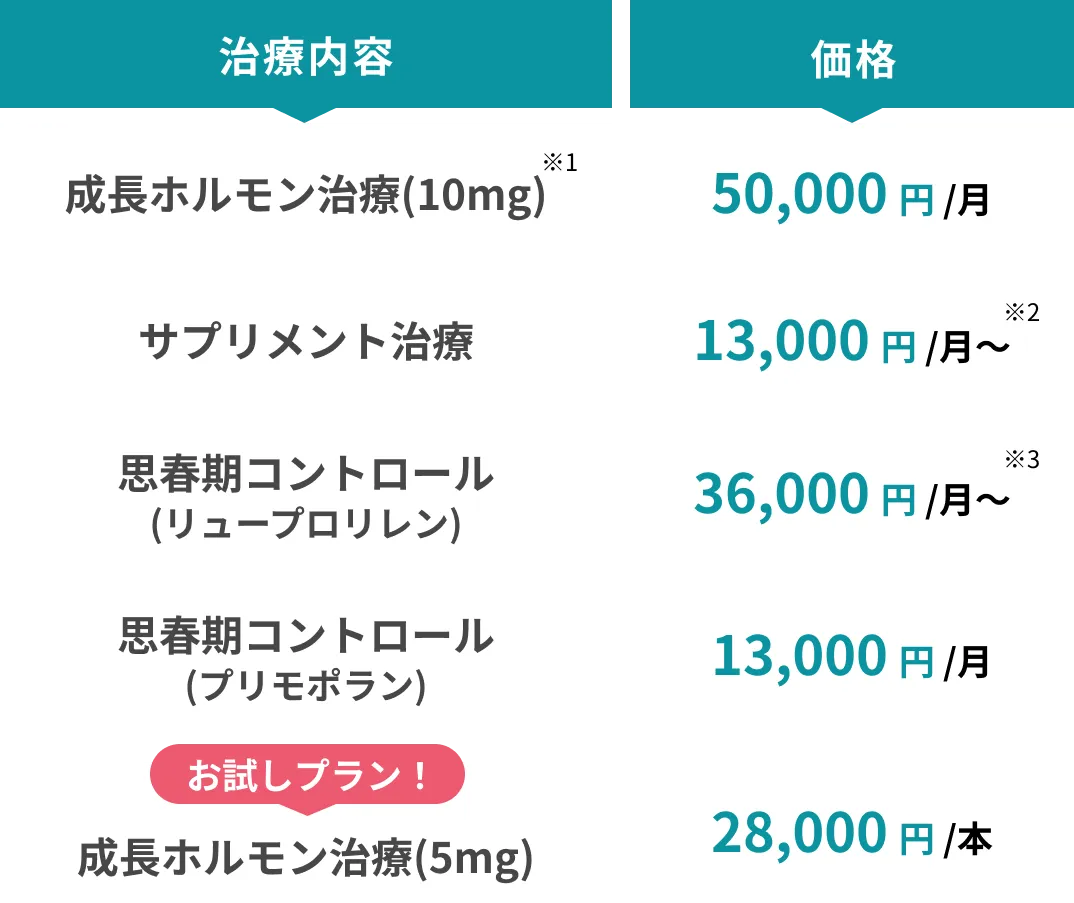

本来体内で生成される成長ホルモンを、注射で外部から補充する治療方法です。身長が伸びる速度が向上する最も効果が期待できる方法です。

成長ホルモンの作用に影響する鉄、亜鉛、ビタミンDなどの栄養は不足しがちなため、サプリメントでの補給が身長の伸び率維持に役立ちます。

ホルモンの働きを調整することで、思春期の進行を緩やかにして、身長が伸びる期間を長く保てるようにします。

治療期間に縛りはありませんが、最低1年間の継続をお勧めしています。

3か月だけでも治療は可能ですが、お勧めは出来ません。治療自体は可能とも⾔えますが、最低1年は治療することをお勧めします。

再診は原則として3ヶ月に1度お越しいただいており、⾎液検査も実施します。気になることがあった時に受診も可能です。

※再診料は5,500円、⾎液検査は15,000円